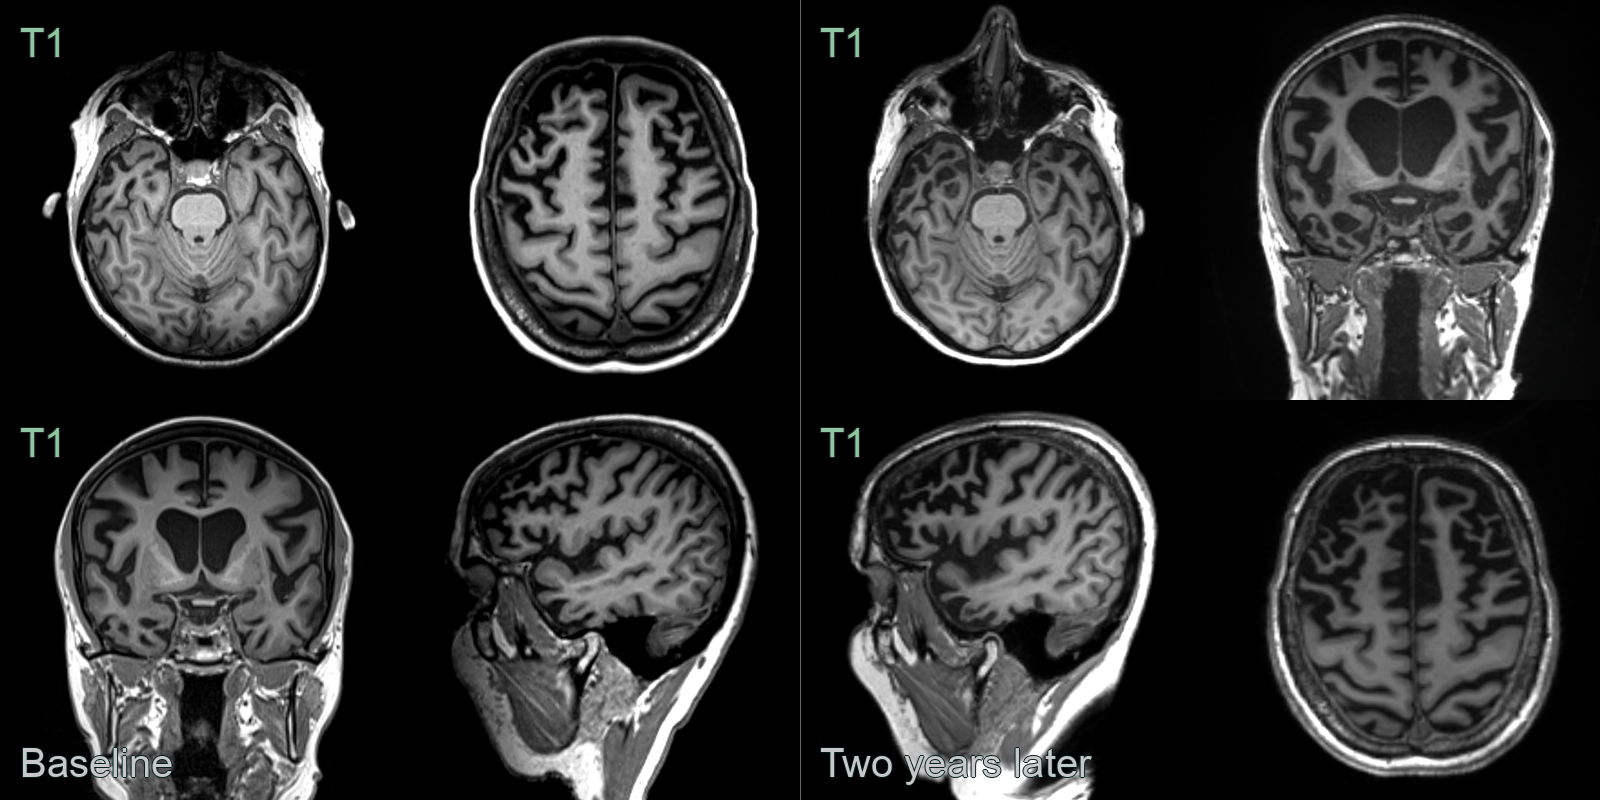

- A 60-year-old patient presented with disinhibition and impaired naming and verbal memory.

- MRI showed pronounced anterior temporal, milder left parietal, and no frontal lobe atrophy. There was particularly pronounced atrophy of the amygdalae.

- CSF amyloid markers were normal, making Alzheimer's disease unlikely. Genetic testing revealed a MAPT mutuation as the cause of frontotemporal dementia.